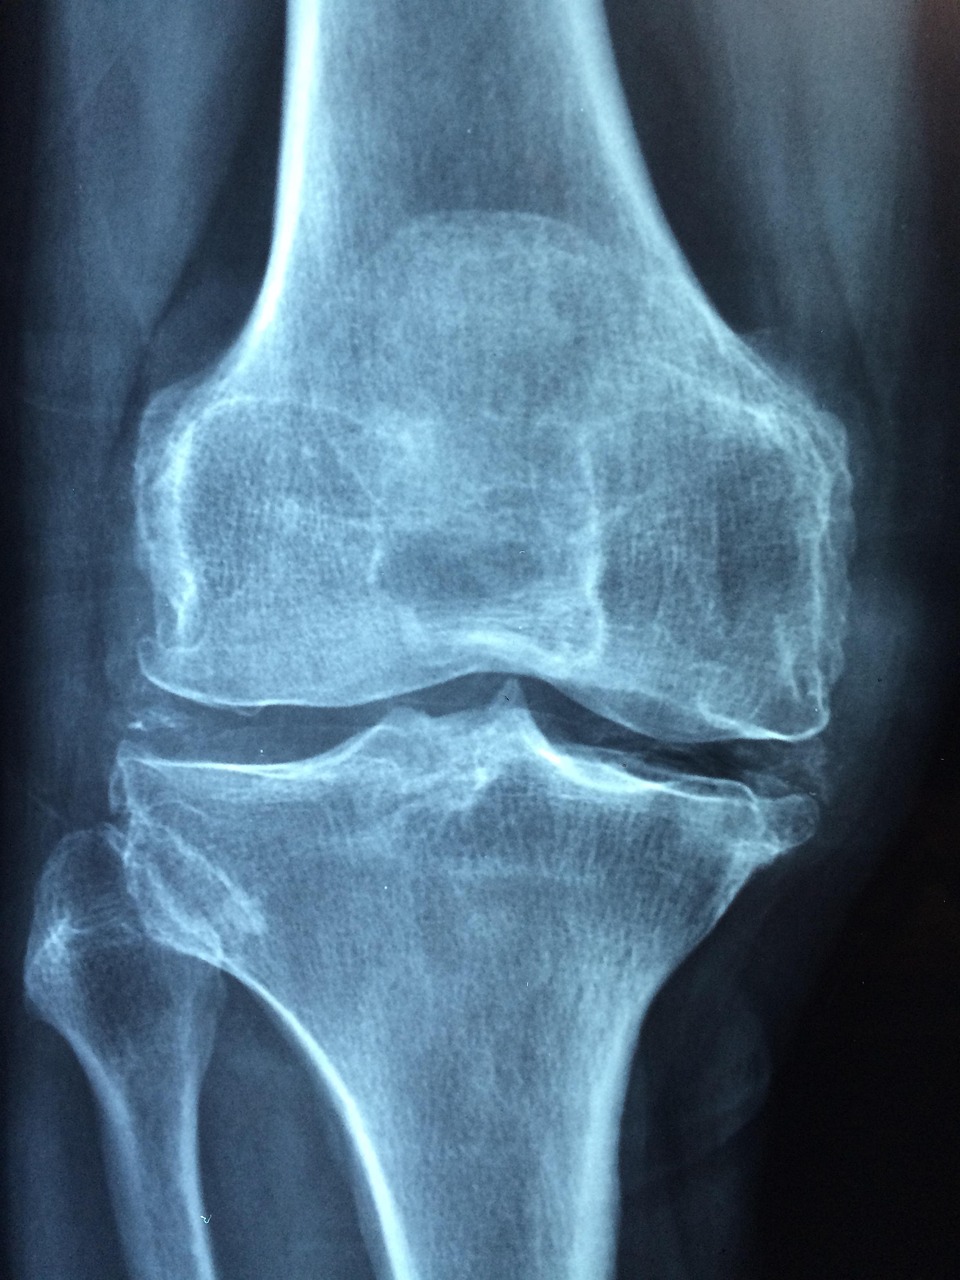

5. 검사 방법 (DXA·QUS)

| 검사 방법 | 특징 | 장점 | 단점 |

|---|---|---|---|

| DXA (이중에너지 X선 흡수계측법) | 요추·대퇴골 촬영 | 정확도 최고, 국제 표준 | 방사선 노출, 비용↑ |

| QUS (정량적 초음파) | 발뒤꿈치 초음파 | 간단·저렴, 방사선 無 | 정밀도 낮음 |